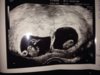

Tvillinger <3

Gratulerer!!! Herremin så herlig! Kan hende det er to inni magehuset mitt også siden HCG var så høy og jeg har satt inn to befruktede egg :) dobbel glede kaller jeg det ❤️❤️❤️